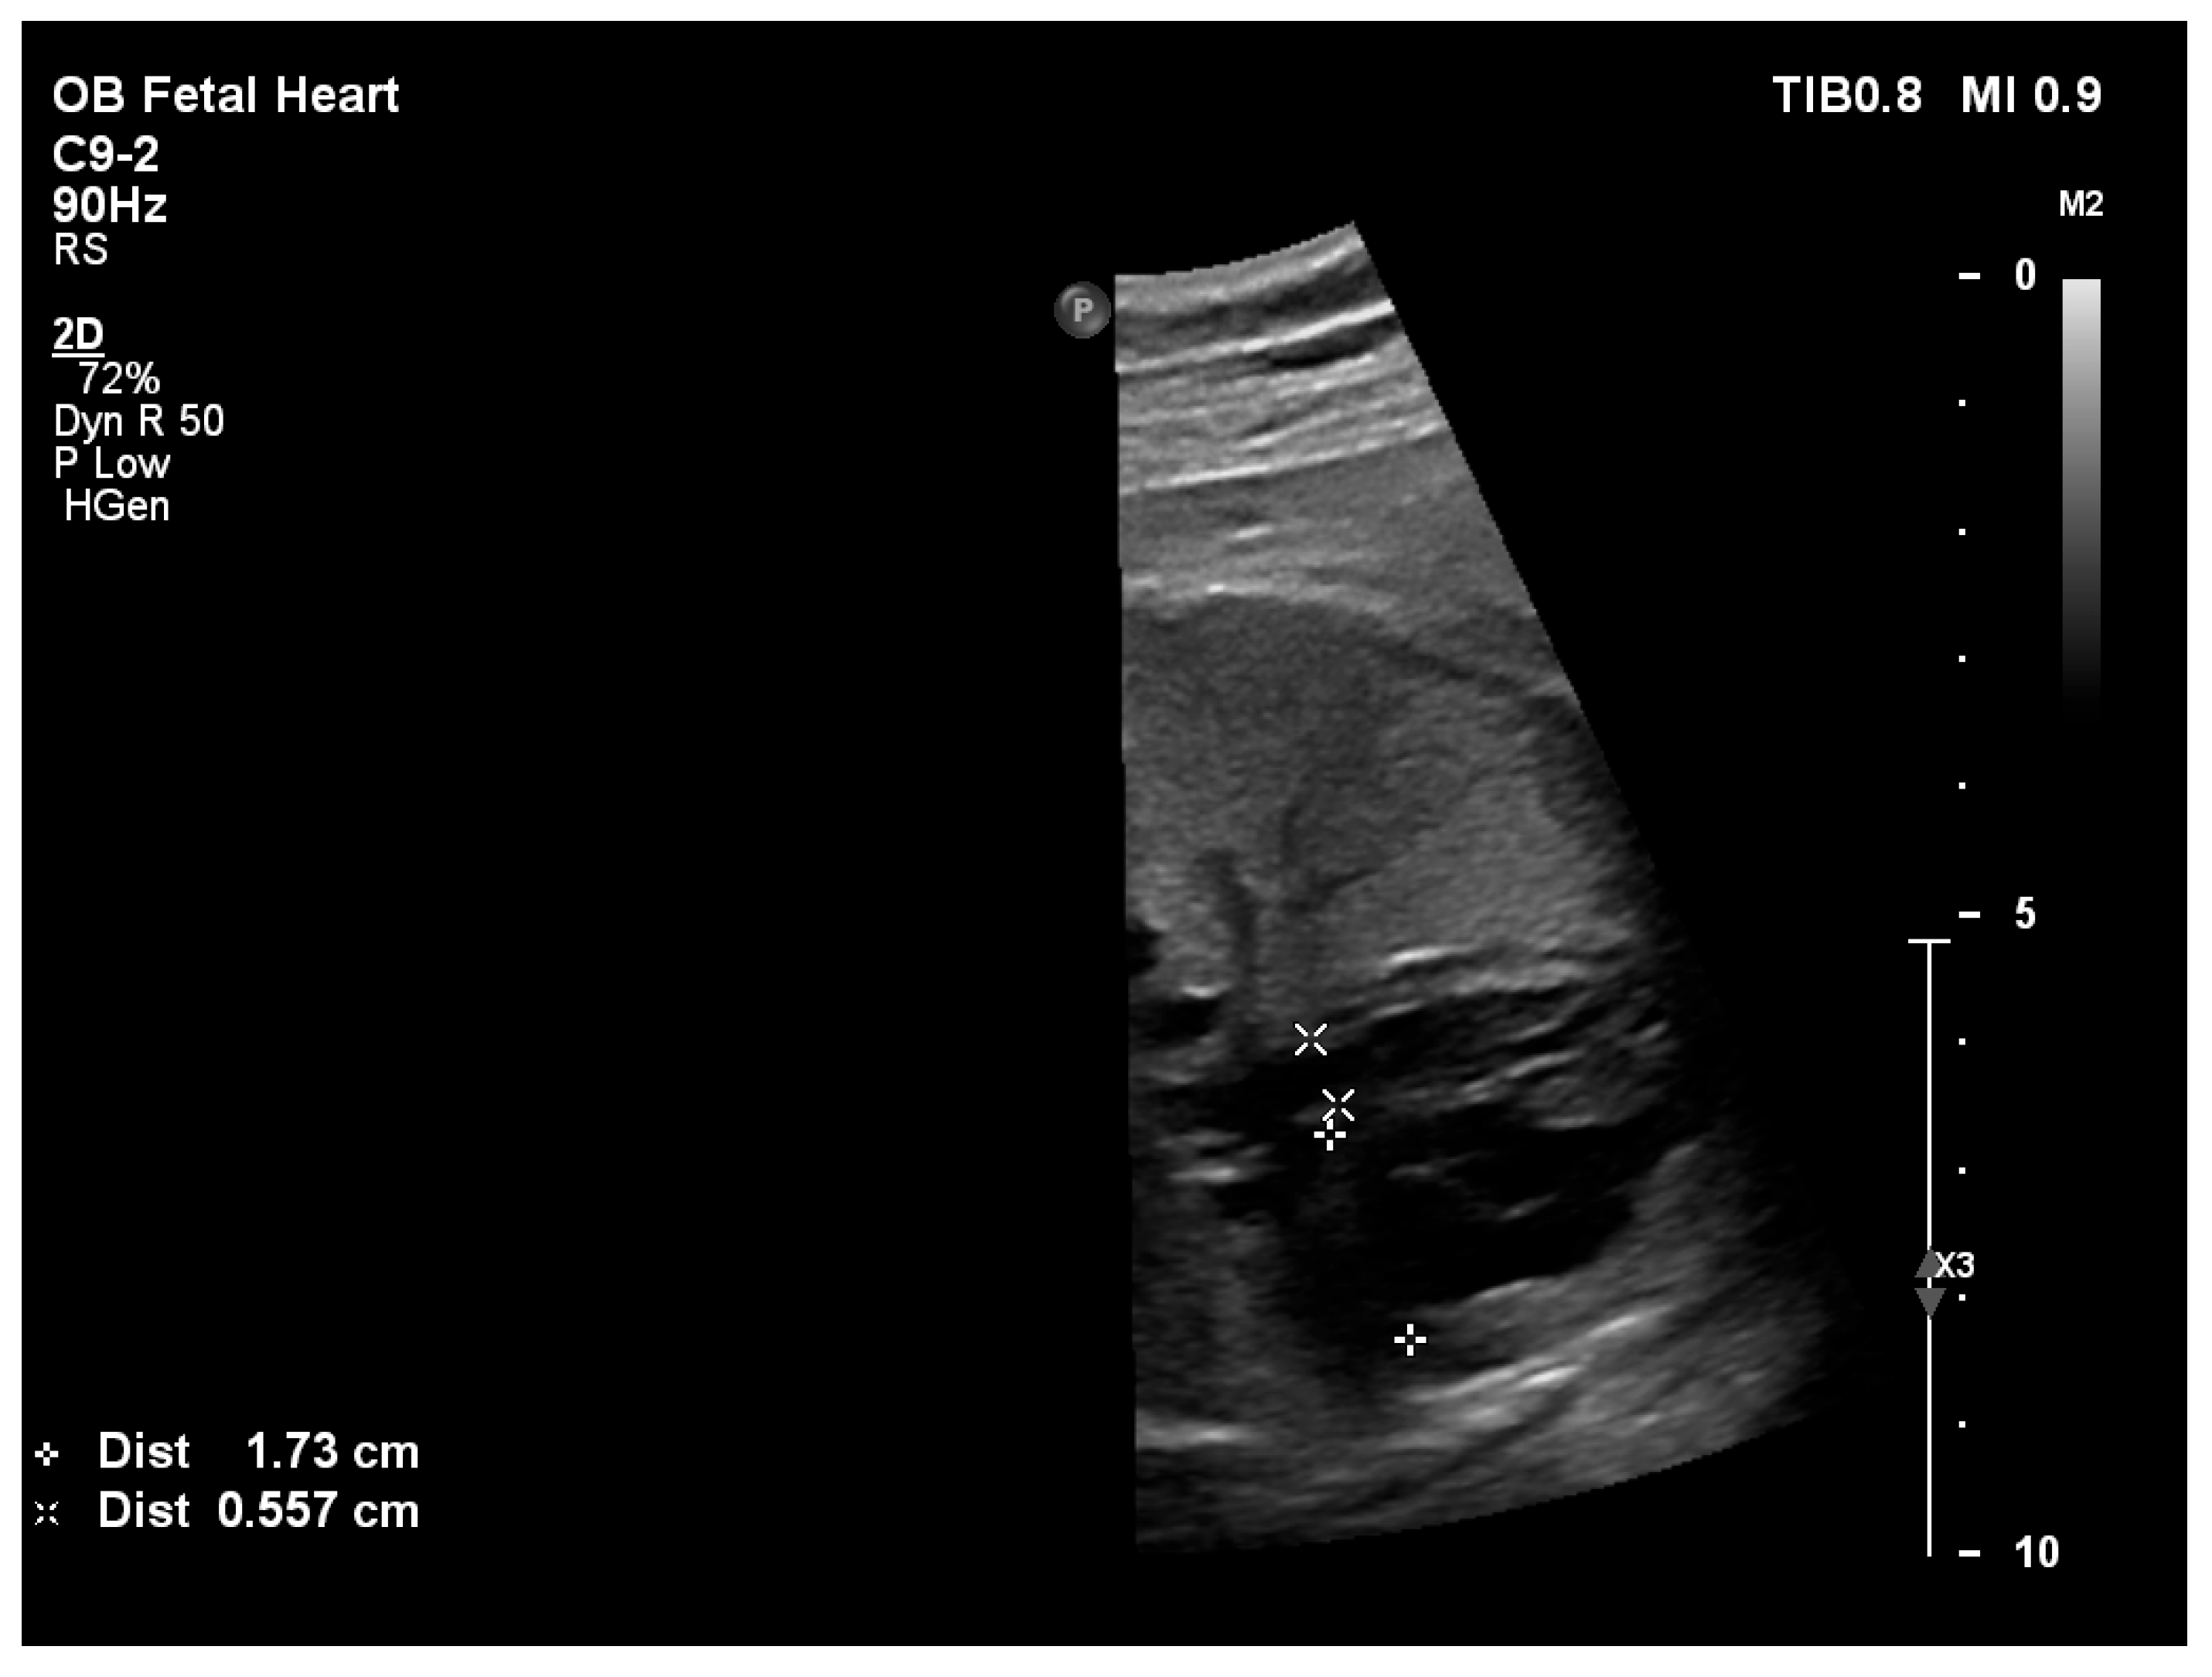

| Aortic isthmus Z-score | −3.46 | −3.43 | −3.40 | Z-score < −3 consistent with severe arch hypoplasia/coarctation |

| Restrictive atrial septal defect | No | No | No | Restriction suggested by high-velocity atrial shunt and LA hypertension |

| Atrial septal defect (mm) | 6 | 3 | 3 |

| Direction of atrial shunt | Left-to-right | Left-to-right | Left-to-right |